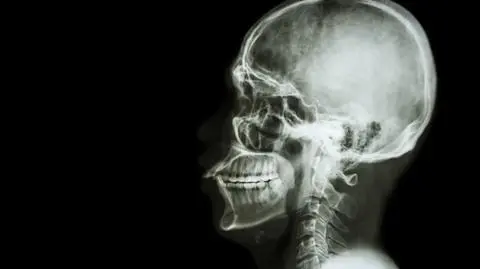

Kichanie może okazać się groźne dla zdrowia

Powstrzymanie kichnięcia może zagrażać życiu

Po wykonaniu prześwietlenia lekarze stwierdzili, że u pacjenta doszło do poważnego urazu. Stwierdzono odmę, czyli przedostanie się powietrza do tkanek ciała, w których powietrza tego nie powinno być. Tomografia komputerowa wykazała ponadto głębokie na pół centymetra pęknięcie tchawicy między trzecim a czwartym kręgiem piersiowym.